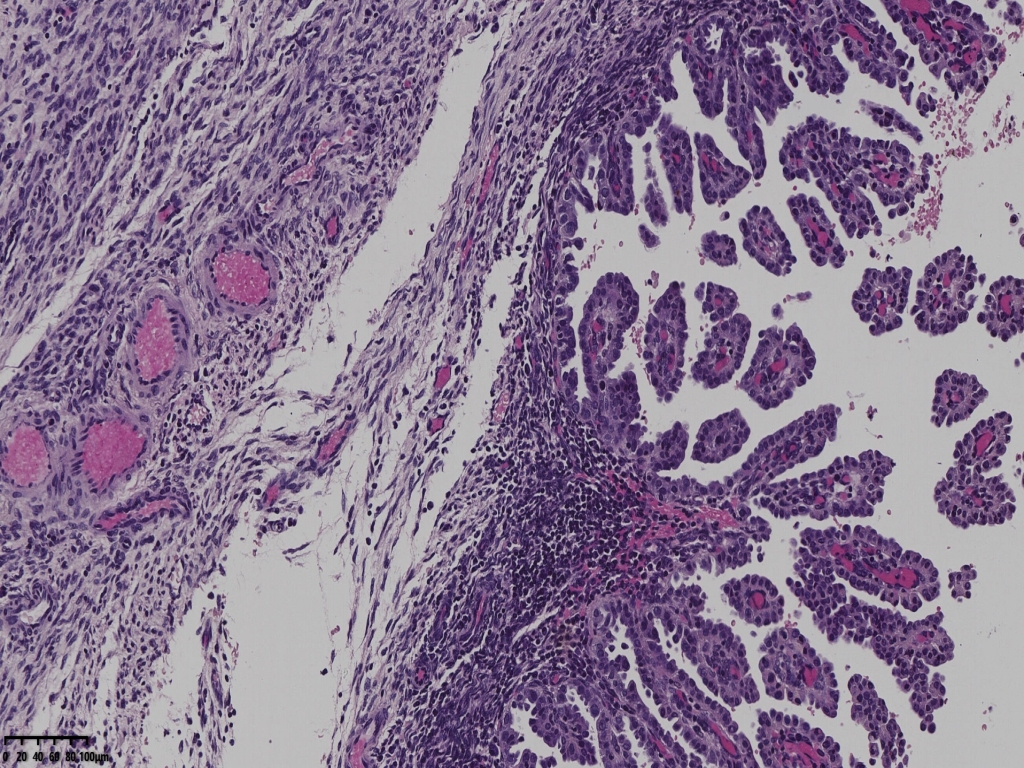

但是其余部位内膜可见微乳头结构。

宫颈管及宫颈管可见癌组织侵犯浅层,以腺样结构为主

癌组织侵及子宫壁浅层,小于1/2,累及宫颈浅层。